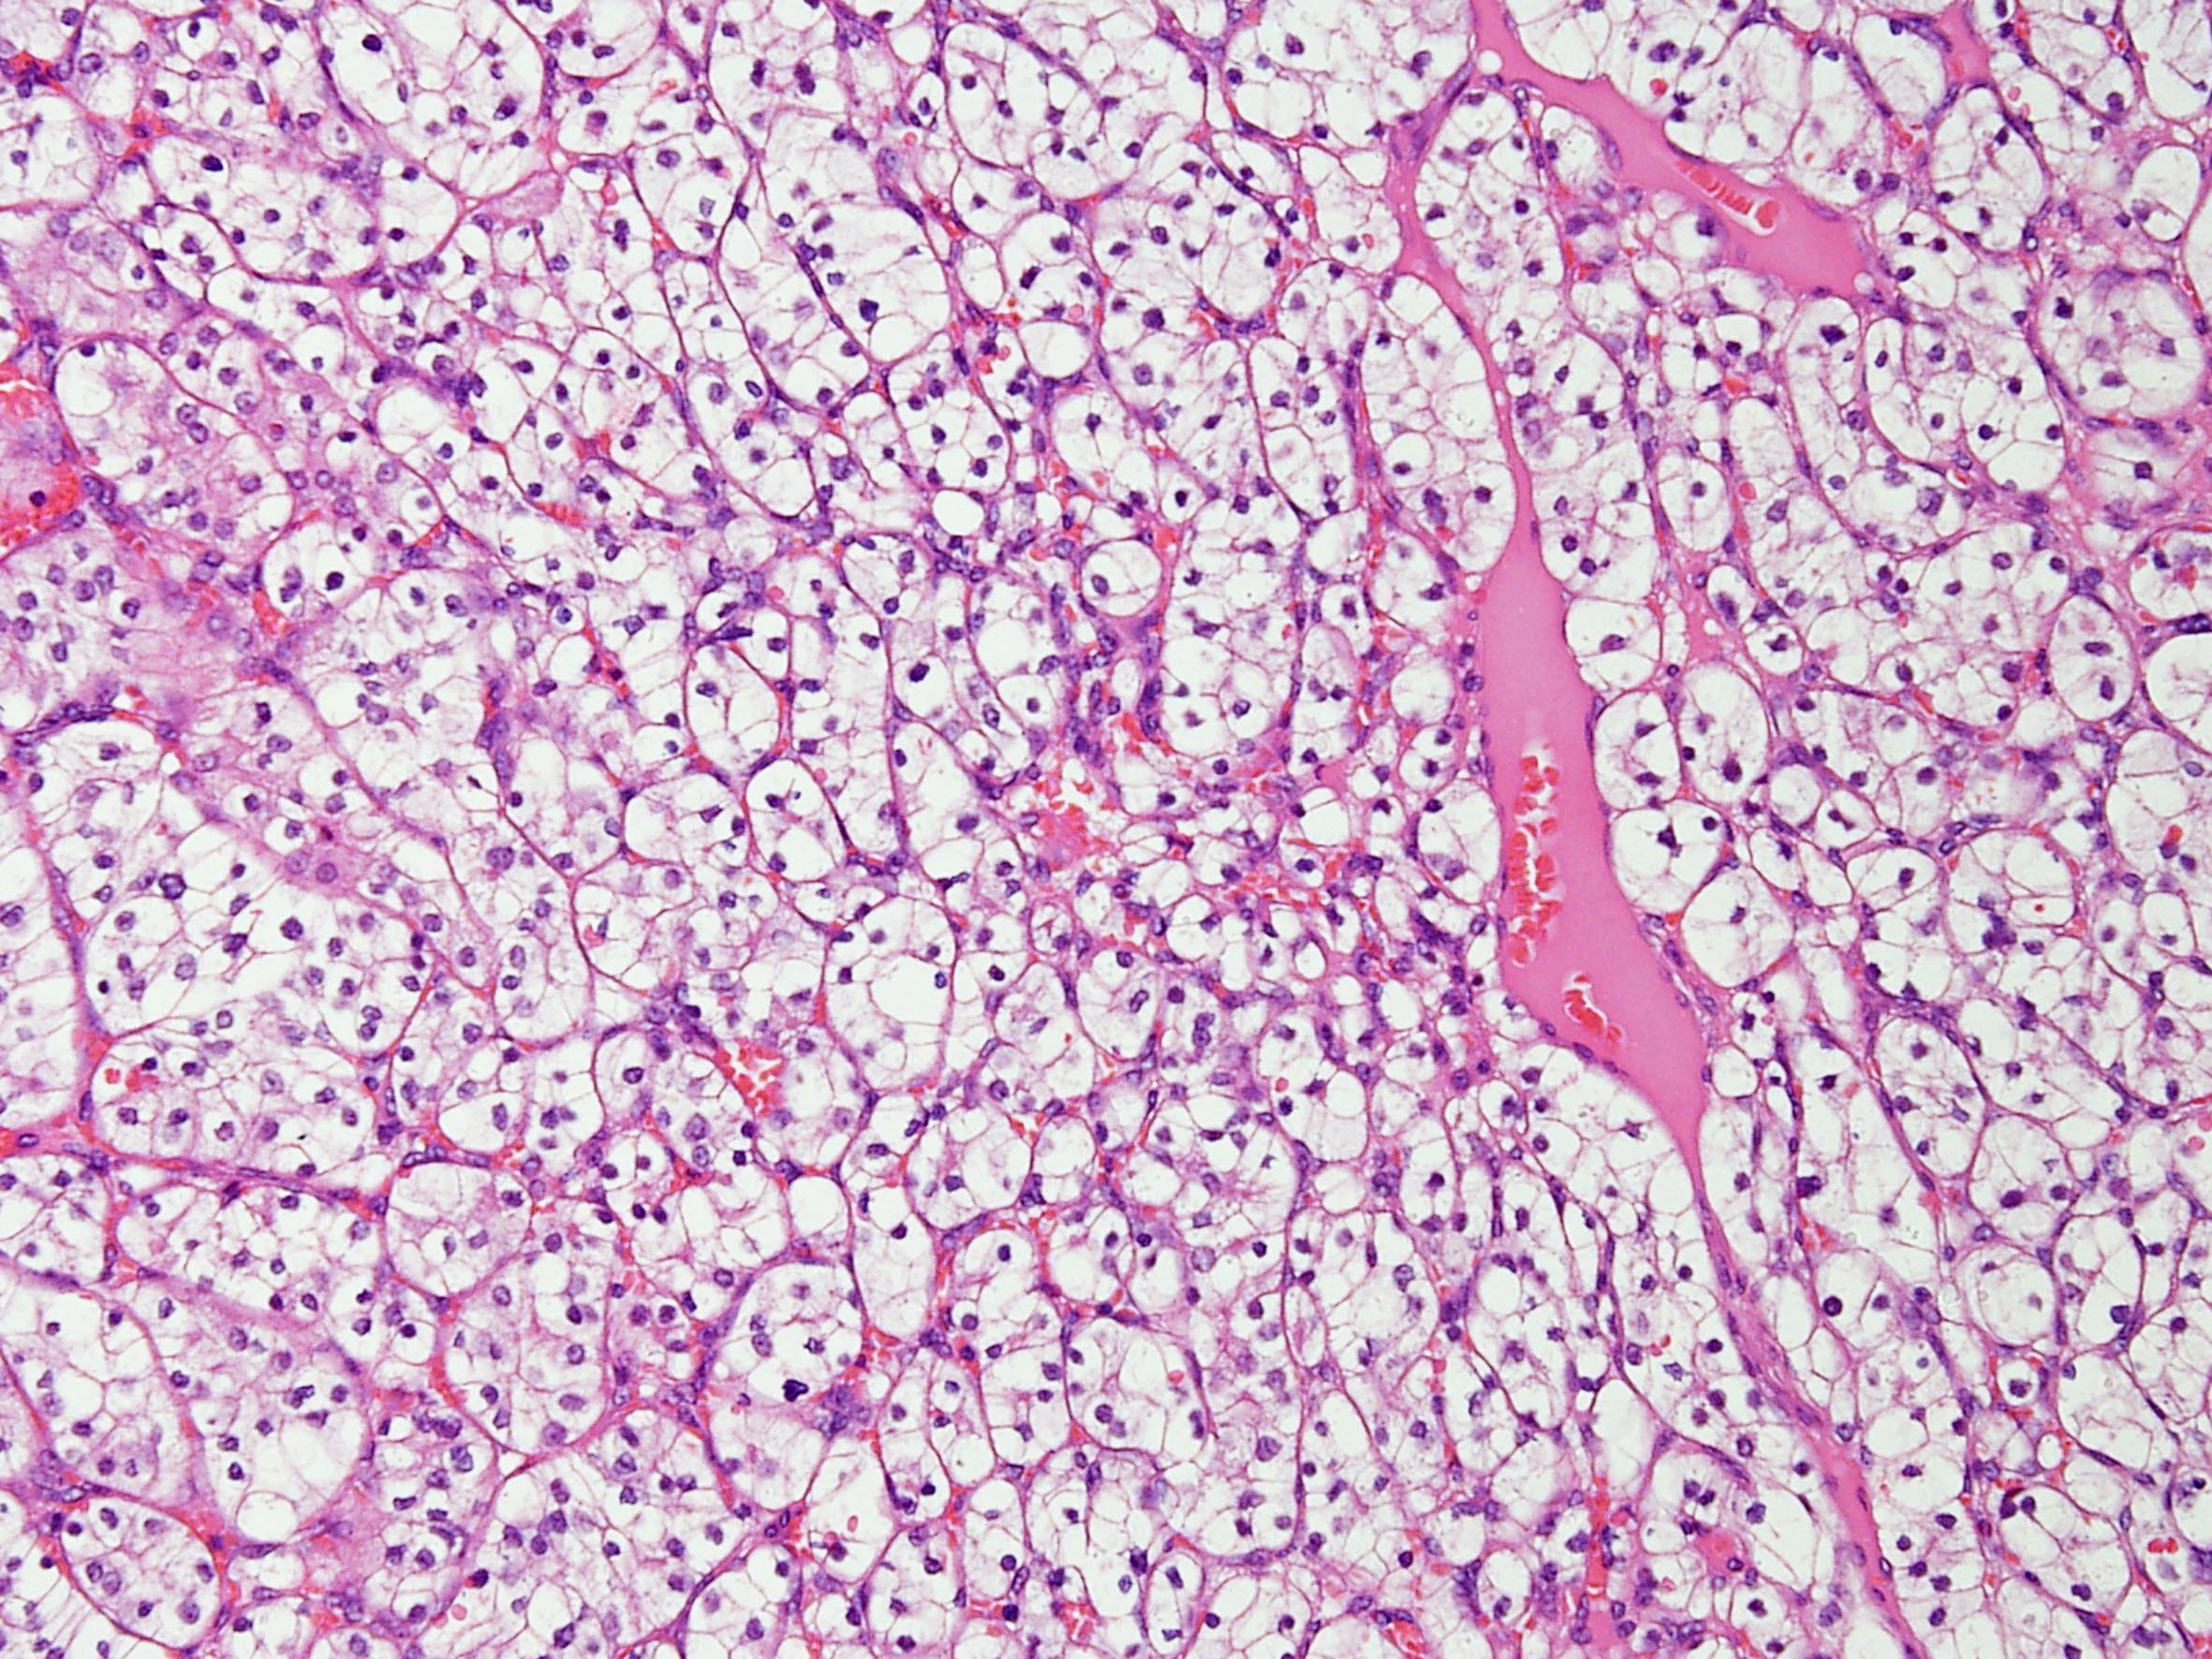

Classification of renal tumors

Case ID: 184